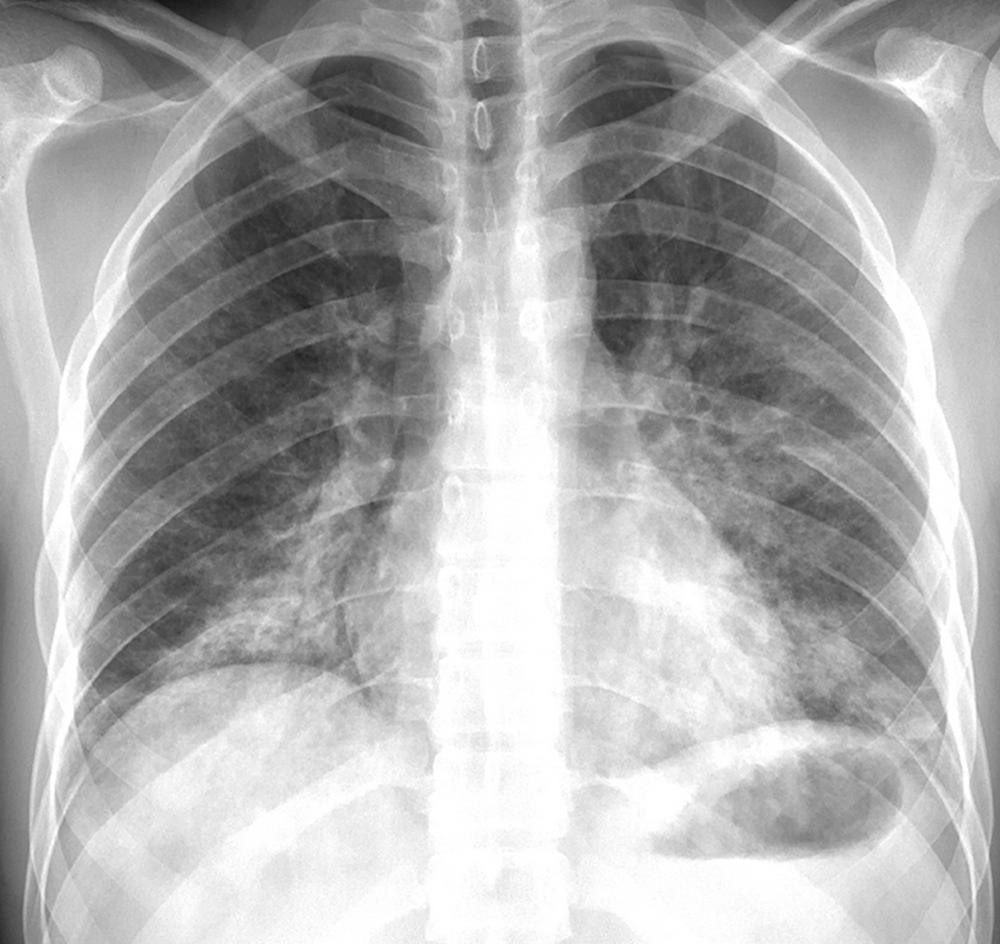

Figure 7 (from Radiology: Cardiothoracic Imaging). Posteroanterior chest radiograph in a 24-year-old man with a history of e-cigarette use shows bilateral reticular and predominantly ground-glass and airspace opacities distributed throughout both lower lungs and absence of pleural effusions.